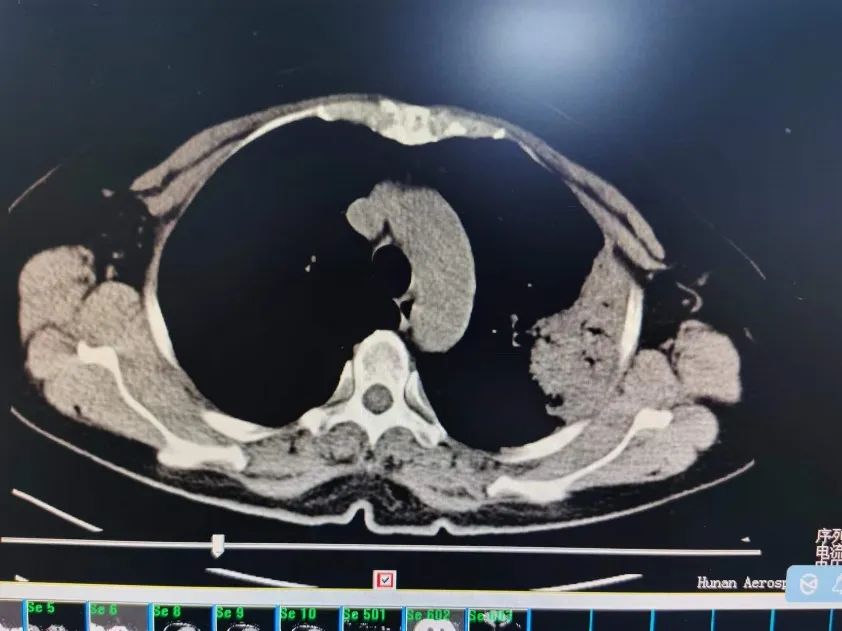

根據(jù)疫情防控的要求,謝阿姨看了發(fā)熱門(mén)診,發(fā)熱門(mén)診為謝阿姨做了新型冠狀病毒核酸檢測(cè),排除新型冠狀病毒感染,同時(shí)為謝阿姨安排了血常規(guī)、肺部CT檢查。結(jié)果提示謝阿姨發(fā)熱可能是因?yàn)榉尾扛腥疽鸬,發(fā)熱門(mén)診的醫(yī)生遂給謝阿姨開(kāi)了呼吸與危重癥醫(yī)學(xué)科的住院證。

圖片圖片

謝阿姨肺部病變區(qū)域

呼吸與危重癥醫(yī)學(xué)科劉斌主治醫(yī)師接診了謝阿姨,仔細(xì)看了謝阿姨的肺部影像后,劉醫(yī)生問(wèn)“阿姨,您家平時(shí)有養(yǎng)雞、鴨、鳥(niǎo)類(lèi)等家禽類(lèi)動(dòng)物嗎?”,謝阿姨兒子立馬答道,“我媽最近買(mǎi)了兩只鴿子,前幾天無(wú)緣無(wú)故死了”。就是這樣一句話,劉斌醫(yī)師立馬將謝阿姨的發(fā)熱鎖定了一個(gè)疾病——鸚鵡熱。

為了驗(yàn)證自己的診斷,劉醫(yī)生很快給謝阿姨安排了抽血化驗(yàn),一天后,結(jié)果顯示:血液中檢測(cè)出鸚鵡熱衣原體。謎底揭開(kāi),劉醫(yī)生很快為謝阿姨調(diào)整了抗生素方案,幾天后,謝阿姨體溫正常了,7天后復(fù)查肺部CT,肺部感染病灶基本吸收,謝阿姨開(kāi)心出院了。